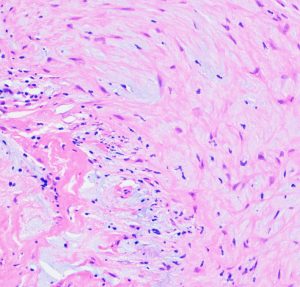

病理所見では,幼児型のpilomyxoid astrocytomaの部分が混在します。その部分が増殖と腫瘍増大に関わっています。T2強調画像で高信号でガドリニウム増強される部分です。

myxoidな部分です。右下のMIB-1染色では3%ほどの陽性率であり,数年単位では腫瘍増大があり得ることを示します。柔らかく出血性で吸引摘出できる部分の腫瘍です。IDH wild type, BRAFV600 wild type, H3K27 wild type, FGFR1 N546K mutationでした。

厚く肥厚した視神経鞘の内部の視神経組織はほとんど腫瘍に置き換わっていて,GFAPで染色され高度の石灰化を伴います。これは腫瘍というよりも瘢痕化してしまった,adult-type pilocytic astrocytomaに認められる所見です。

Rosenthal fiber, eosinophyric granular body, psammoma bodyなどが認められ,成熟しきって退行変性に移行するpilocytic astrocytomaの像です。この部分は増大しません。線維性に極めて硬い組織です。